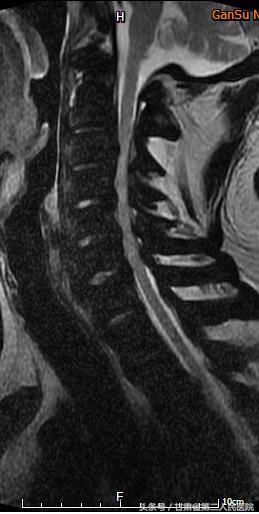

入院后行全脊柱X线、CT及MRI示:C3-6颈椎后纵韧带骨化引起的脊髓型颈椎病,并有严重的石骨症。

可见后纵韧带骨化

术前